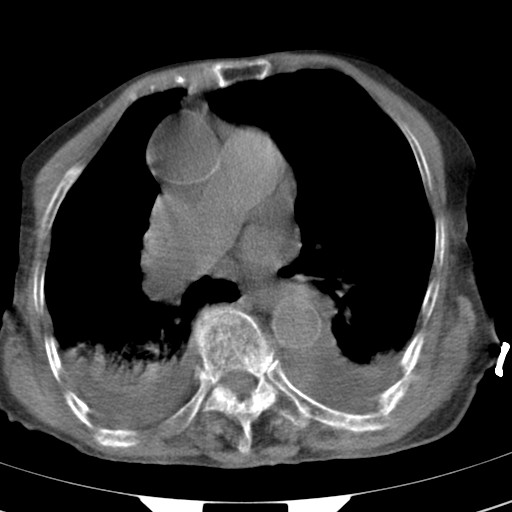

标题: CT21467:女,93岁,摔伤后检查。

女,93岁,摔伤后检查。

食管裂孔疝

创伤性湿肺,双侧胸腔积液。可能有食管裂孔疝,进一步检查。骨折有无根据自己的机器及片子再仔细看吧。

右侧锁骨\\肩胛骨骨折、右侧湿肺,心功能不全伴双侧胸腔积液,右下肺膨胀不全,左膈破裂或食管裂孔疝,冠脉钙化,心包少量积液,请上传骨窗.

右肺炎症,心功能不全伴双侧胸腔积液,右下肺膨胀不全,食管裂孔疝,冠脉钙化,心包少量积液,左侧肋骨骨折,右肩甲骨粉碎性骨折。93岁,高寿哇!